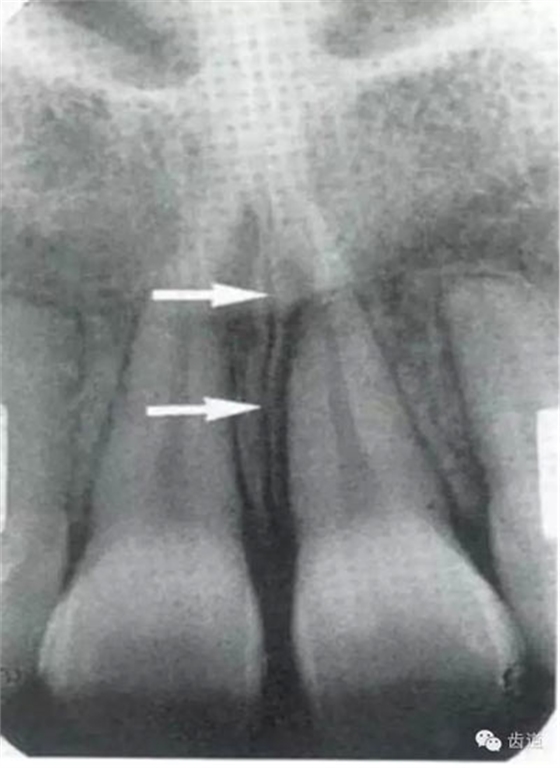

位于兩側(cè)中切牙牙根之間,由牙槽突向上,呈直線狀密度低的影像。其兩側(cè)為密度高的影像,為兩側(cè)上頜骨腭突的致密骨層。